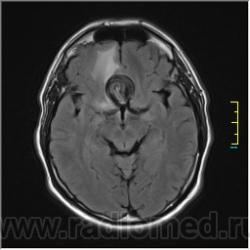

Пациентка направлена на исследование с диагнозом "Гипертонический криз", энцефалопатия неуточненная.

Ax T2 Flair:

частично функционирующая аневризма

Иначе говоря, аневризма с хронической геморрагией, т.к. мы видим фракции крови различного возраста.

По-моему, аневризма с пристеночными тромбами.

Постепенное пристеночное образование тромбов приводит к появлению типичного для аневризмы феномена -слоистости МР сигнала в полости аневризмы. Данная картина демонстрирует слоистый характер тромботических масс в полости аневризмы .Функционрирующая часть имеет низкий сигнал во всех режимах сканирования. Дополнительно-перифокальный отек.

А может более корректно интерпретировать как частично тромбированная аневризма... Уж коь речь идет о фракциях, ну то есть о тромбе по сути.... Ну и плюс перфокальный отек головного мозга (вероятнее цитотоксический+вазогенный).